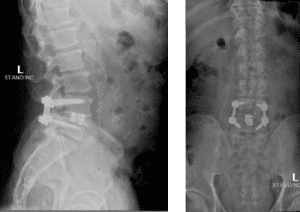

His MRI lumbar spine showed a herniated disc at L2/L3 and a grade 1 spondylolisthesis at L4/L5. Both of these findings were contributing to the patients back and leg pain.

The grade 1 spondylolisthesis at L4/L5 requires both decompression at the L4/L5 level but also fusion because of the instability with motions. Here are three standing x-rays: one in the neutral position, one in flexion, and one in extensions. Notice the movement in the vertebral bodies at L4 and L5. This is abnormal motion and it can contribute to back pain and increase stenosis in certain positions. Thus, it requires decompression and stabilization with fusions.

Image 2. This shows the lumbar spine in motion. Notice the L4 and L5 level changes with flexion and extension. Notice the L2 and L3 levels do not have that type of motion. This is instability.

Image 3. Post-op x-rays that show L4/L5 transforaminal lumbar interbody fusion (TLIF). There was also removal the L2/L3 disc herniation but no need for instrumentation.